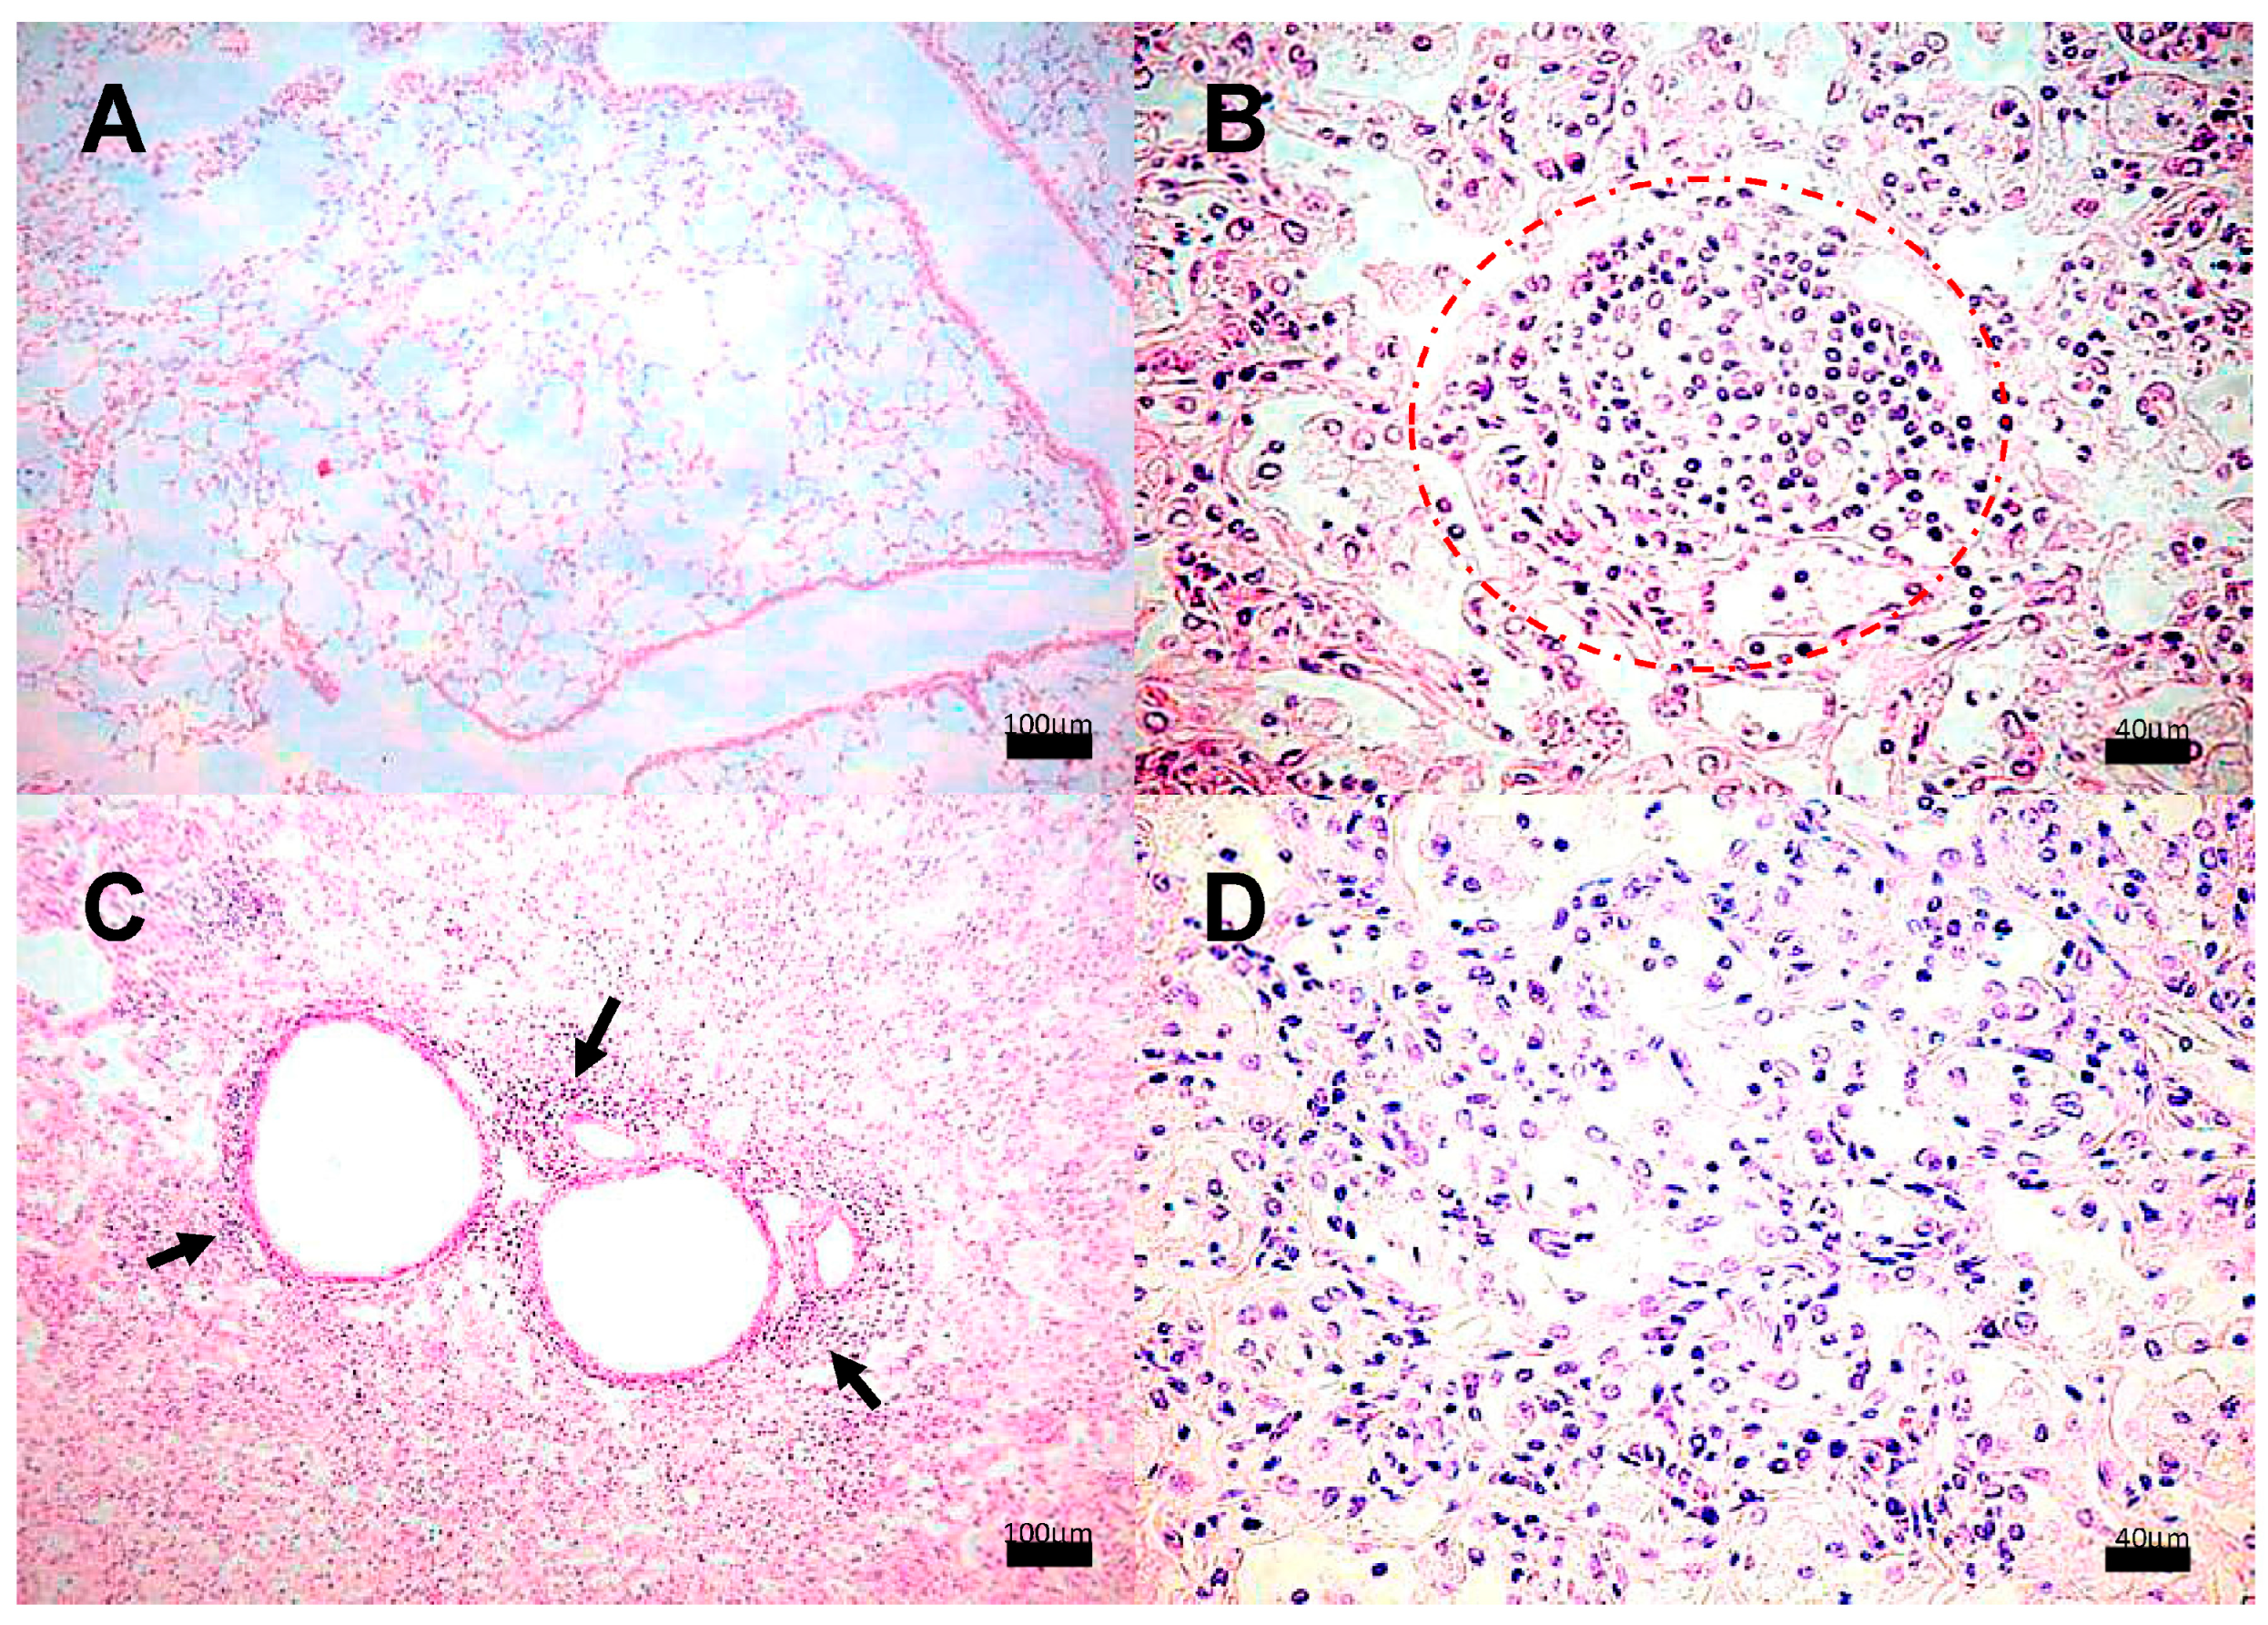

3.2. Encephalon Histology and Bacillary Load